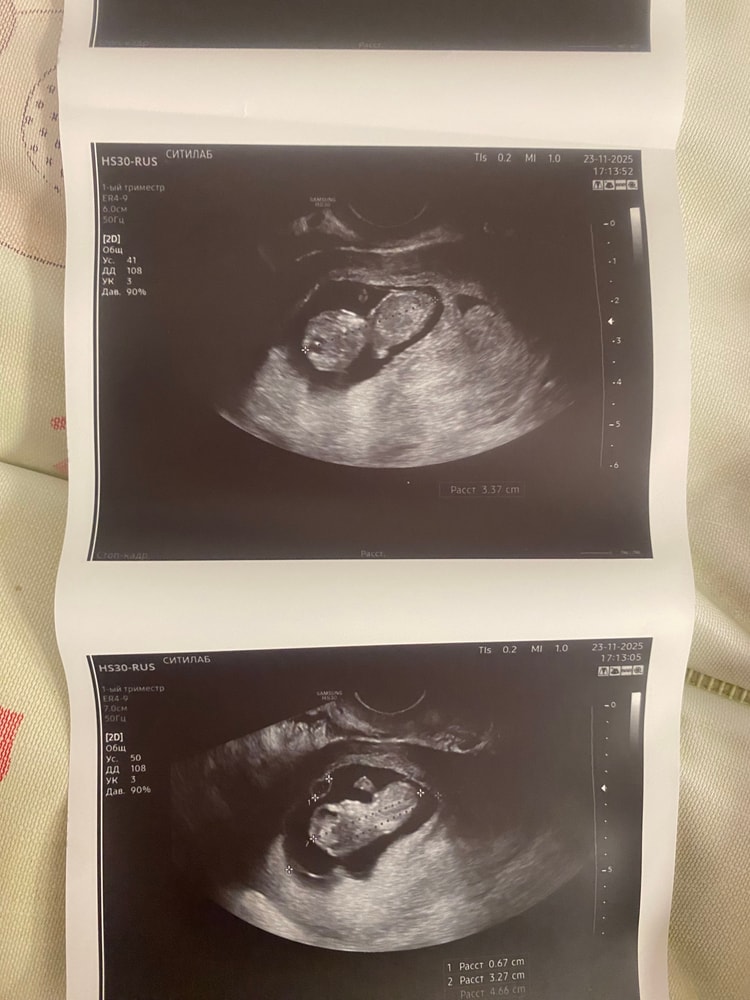

10 недель

Моя ЭКО-история (от начала пути до родов)Всем привет, сегодня сходила на узи

уже большой такой🥺 в 8 недель еще масенткий был, а тут так вырос уже

Догнал слава богу, даже на один день обогнал

Хотя вот на 8 неделе отставал на неделю

Был всего 9,6 мм, а теперь 3 с половиной сантиметра